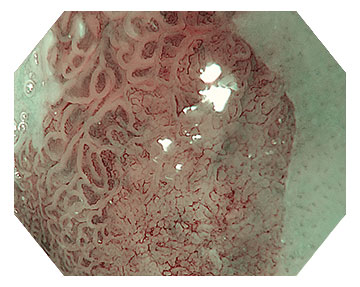

強烈建議在常規白光內視鏡之外,搭配影像增強技術來改善黏膜細節的可見度,例如窄頻影像 (NBI),藉此顯著提升腸化生(GIM)區域的對比度與檢出率。紋理色彩增強影像(TXI)則能夠增加胃癌前病變與早期胃癌病灶的可見度,縮短診斷時間。

當白光內視鏡下發現可疑的局部腫瘤性病灶時,應進一步使用高畫質影像增強技術,最好搭配近焦觀察功能,結合NBI評估病灶是否有明確邊界,以及不規則的微血管或微表面結構,藉此精準區分早期胃癌與非癌病變。